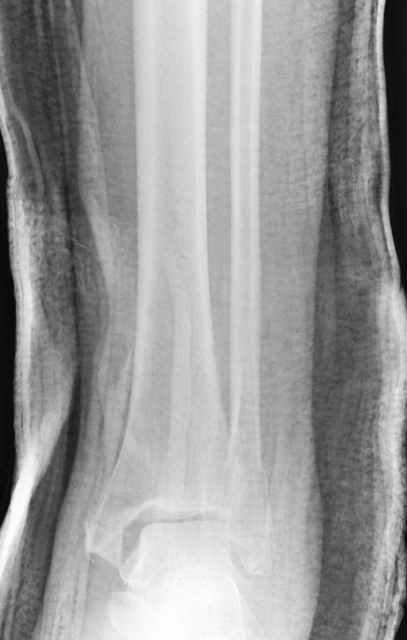

Техника сегодня более щадящая, временные несложные аппараты наружной фиксации: Spanning 2 pin ExFix, Traveling traction для лигаментотаксиса, иначе сокращенные мягкие ткани невозможно восстановить позже.

За последнее 10-12 лет после стабилизации малоберцовой кости, стали применять более усовершенный, сложный, хорошо вам известный метод

Илизарова (кстати наряду с тибиал плато, пилон является одним из показанием по применению аппарата Илизарова при травмах) или Hybrid

Fixator, из минимальных доступов комбинированный метод для восстановления суставной поверхности-фиксация каннулированными

шурупами, создания жесткой системы фиксации до сращения перелома, защита от вальгусной деформации и на место образовавщегося метафизарного дефекта- костная пластика ауто костью или его

синтетические заменители, это сегодняшная тактика лечения.